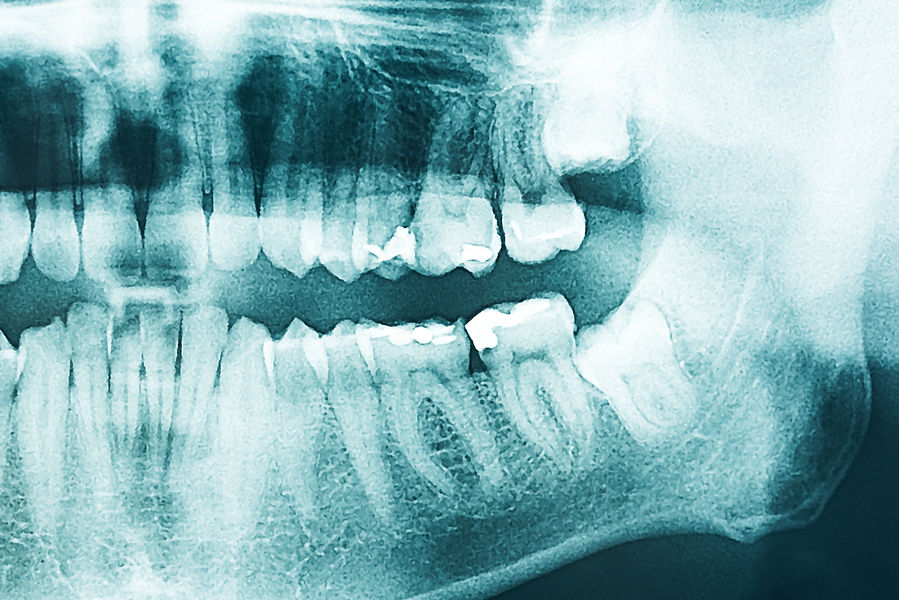

Einen letzten Versuch, wurzelkanalbehandelte Zähne zu retten, stellt die Wurzelspitzenresektion dar. Hierbei wird unter Lokalanästhesie, mit Hilfe des Operationsmikroskopes, die Wurzelspitze entzündeter Zähne vorsichtig und durch ein kleines Fenster im Knochen dargestellt, danach abgetrennt und die Infektion auf diese Weise beseitigt.

Um langfristigen Erfolg zu erreichen, muss der Wurzelkanal zusätzlich retrograd , bakteriendicht gefüllt werden (genannt: mikrochirurgische Apexversiegelung oder retrograde Füllung). Als Füllmaterialien verwenden wir ausschließlich MTA (Mineral Trioxid Aggregat) oder biokeramische Materialien. Die Behandlung selbst erfolgt unter optimaler Ausleuchtung und Vergrößerung.